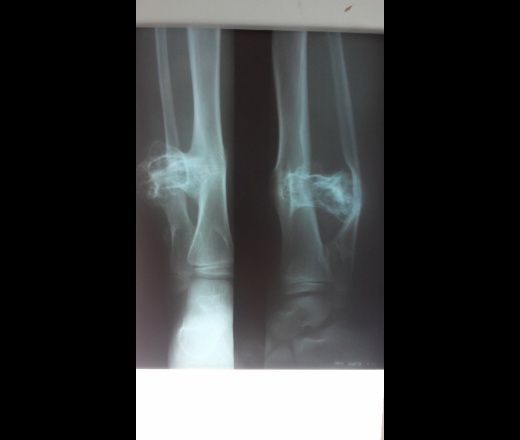

Костные образования.

Со слов мамы: Заболевание врожденное, им так же страдал в детстве его отец, но потом ему сделали "какую то" операцию и все прошло. Образования у ребенка с детства увеличивались стали болезненые. Имеются так же на костях предплечий и грудины.

yes Ещё бы снимочки предплечий и грудины.